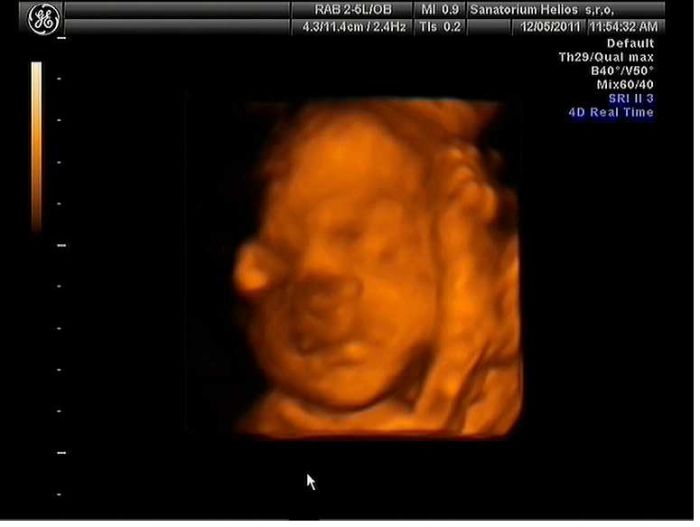

..tady jeste prikladam jediny dve povedeny fotky toho naseho drobecka